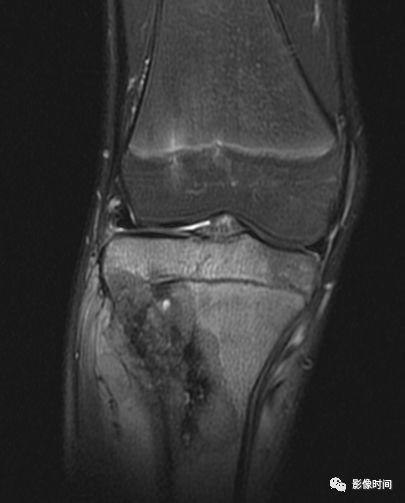

九、瘤周水肿

肿瘤周边的骨髓水肿表现为 T1WT 低信号和 T2WI、STIR 高信号边界模糊的片状影,软组织肿块邻近的正常软组织成分,尤其是肌肉内亦可出现水肿,表现为肿块周围沿肌束方向分布的边界模糊的片状或羽毛状影,有时可连成片。瘤周水肿常见于恶性肿瘤(图 58),但也可见于某些良性肿瘤如软骨母细胞瘤(图 59)、骨样骨瘤和骨嗜酸性肉芽肿(图 60)等。

图 59 瘤周水肿:软骨母细胞瘤